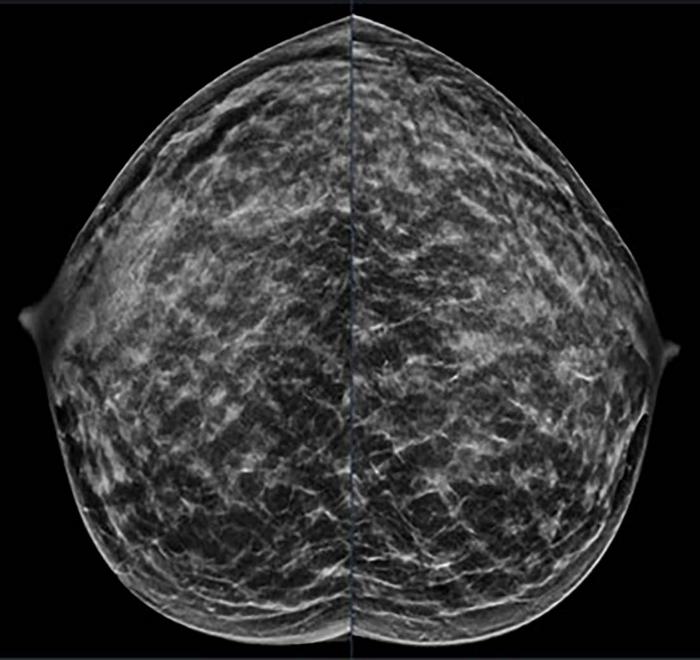

Extremely dense breast tissue is noted on mammography (IMAGE)

40-year-old patient presents for routine screening. Family history of paternal grandmother age 55. Extremely dense breast tissue is noted on mammography right and left craniocaudal (taken from the top of the breast) view.